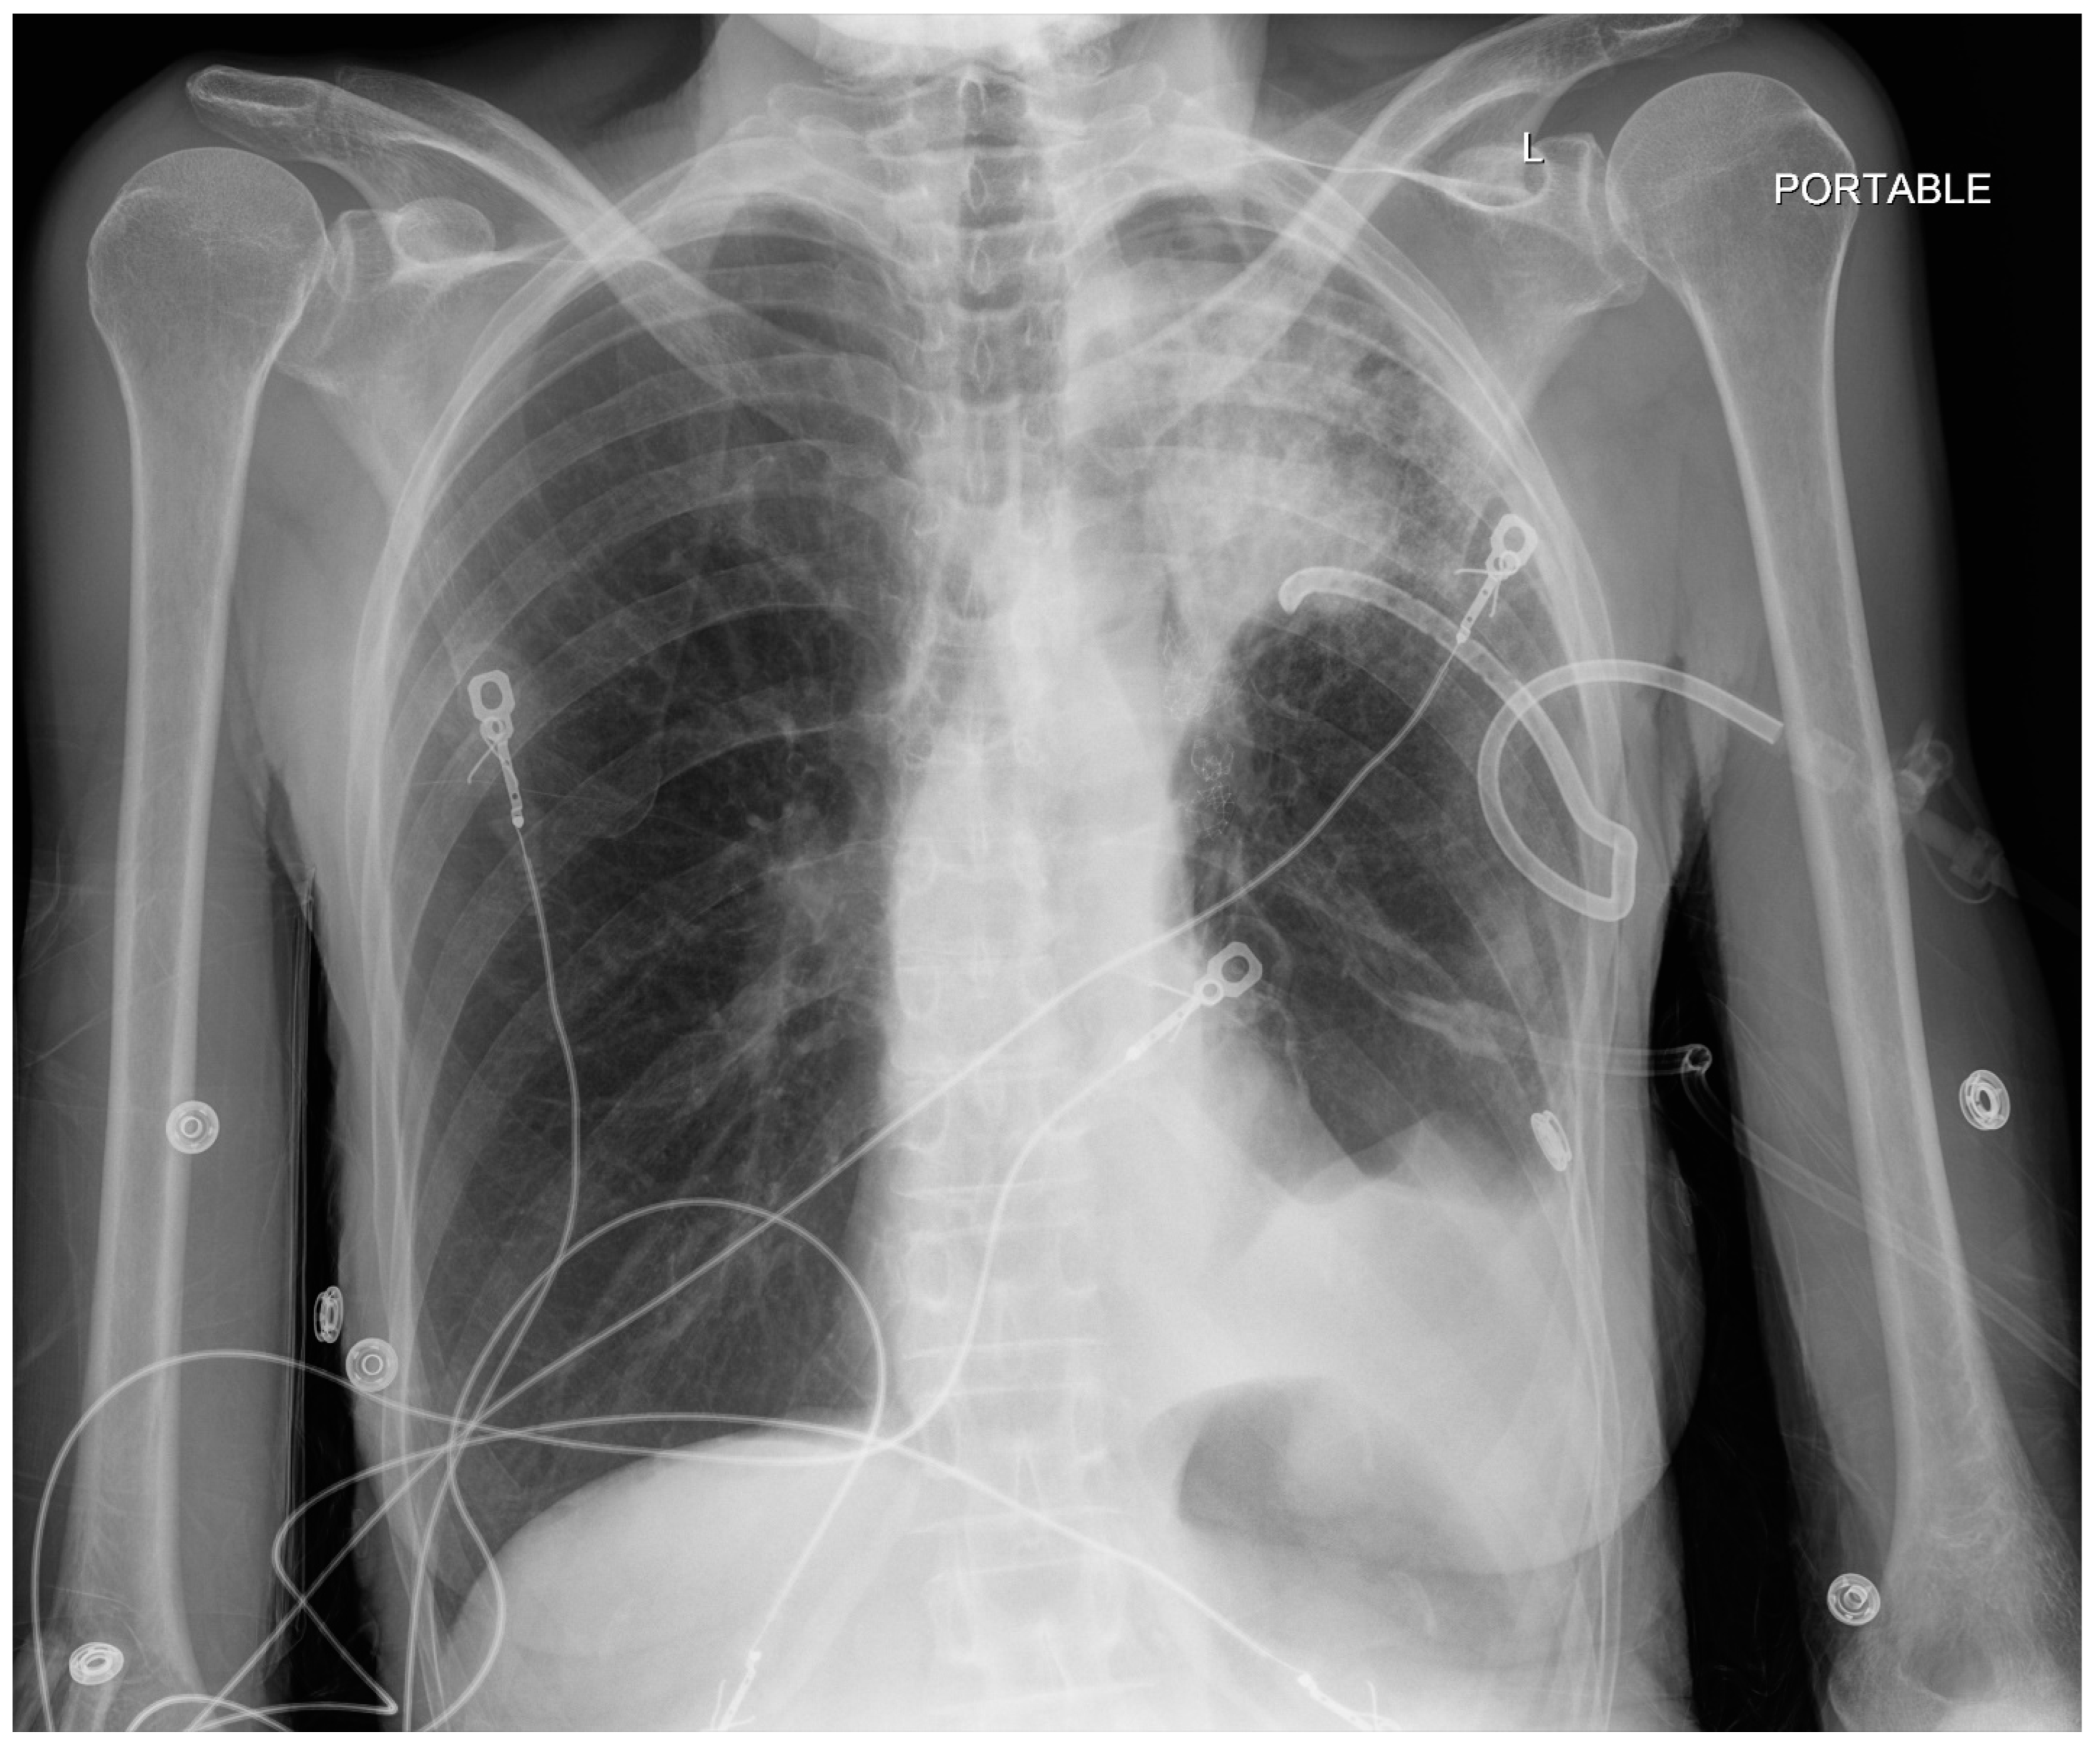

| Procedure | Indication and Preprocedural Factors | Anesthesia Requirements | Post-Procedure Factors |

|---|---|---|---|

| Navigational Bronchoscopy | Biopsying suspicious lesions. Patients are typically elderly with a history of smoking. | General anesthesia, usually TIVA with muscle relaxant. Larger than normal ETT (8.5) Avoid atelectasis without comprising safe oxygenation (SpO2 about 94%). Avoid 100% O2 even for induction. Air O2 mixture for maintenance. ETT position as guided by the bronchoscopist. Use appropriate ventilatory strategy to prevent atelectasis such as VESPA or LNVP (see text for details). Avoid barotrauma and hemodynamic instability during recruitment maneuvers. | Pneumothorax (3.4% to 9.8%). Respiratory failure and difficulty in extubation (rare). |

| Endobronchial valve placement | For lung volume reduction in selected cases of severe COPD | General anesthesia, TIVA with muscle relaxant. Larger than normal ETT (8.5) Hypotension to be expected and often requires phenylephrine support. | Pneumothorax is common, including tension pneumothorax. Incidence is reported as 4.2–34.4% (more often under GA than sedation). COPD exacerbation. |

| Bronchial thermoplasty | Indicated in selected patients with stable asthma without active respiratory tract infection. Should not have exacerbation of asthma for 2 weeks. Before BT, COPD to be excluded. Expect patients to have received steroids before procedure. | General anesthesia, glycopyrrolate for its antisialogogue properties, TIVA with muscle relaxant, ETT or an LMA. | Bronchospasm during or after bronchoscopy. Laryngospasm, atelectasis due to fibrin plugs. Exacerbation of asthma. Lower respiratory tract infections. Bronchial artery pseudoaneurysms. |